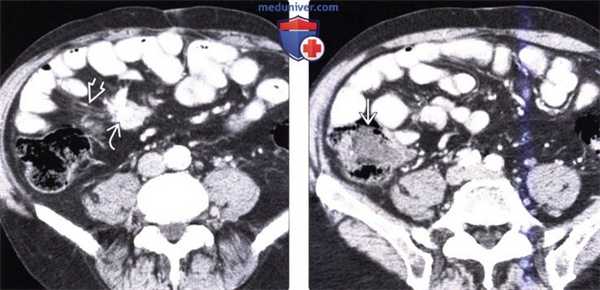

(Слева) На аксиальной КТ с контрастным усилением у мужчины 65 лет с жалобами на боль в животе визуализируется объемное образование в брыжейке с наличием кальцинатов в центре, видны также переполненные кровью брыжеечные сосуды. В правом нижнем квадранте также определяется стягивание брыжейки с деформацией кишечника.

(Справа) На КТ, полученной в венозную фазу контрастного усиления, визуализируется подозрительное объемное образование в илеоцекальной области, которое, как подтвердилось при хирургическом вмешательстве, является карциноидной опухолью. Обычно метастазы в брыжейке более очевидны на КТ по сравнению с первичной опухолью, особенно в венозную фазу контрастного усиления.

(Слева) На аксиальной КТ у мужчины 54 лет со схваткообразной болью в животе и приливами визуализируются гиперваскулярные метастазы в печени и по брюшине.

(Справа) На корональной КТ у этого же пациента визуализируется гиперваскулярное образование в терминальных отделах подвздошной кишки (первичная опухоль) в сочетании с метастазами в брыжейку с наличием десмопластических изменений в брыжейке подвздошной кишки. Эти клинические и лучевые признаки являются классическими изменениями при карциноидном синдроме.